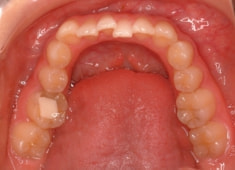

症例紹介

先天欠如歯両側上顎3番

治療法:フルパッシブブラケット:T21

治療開始時